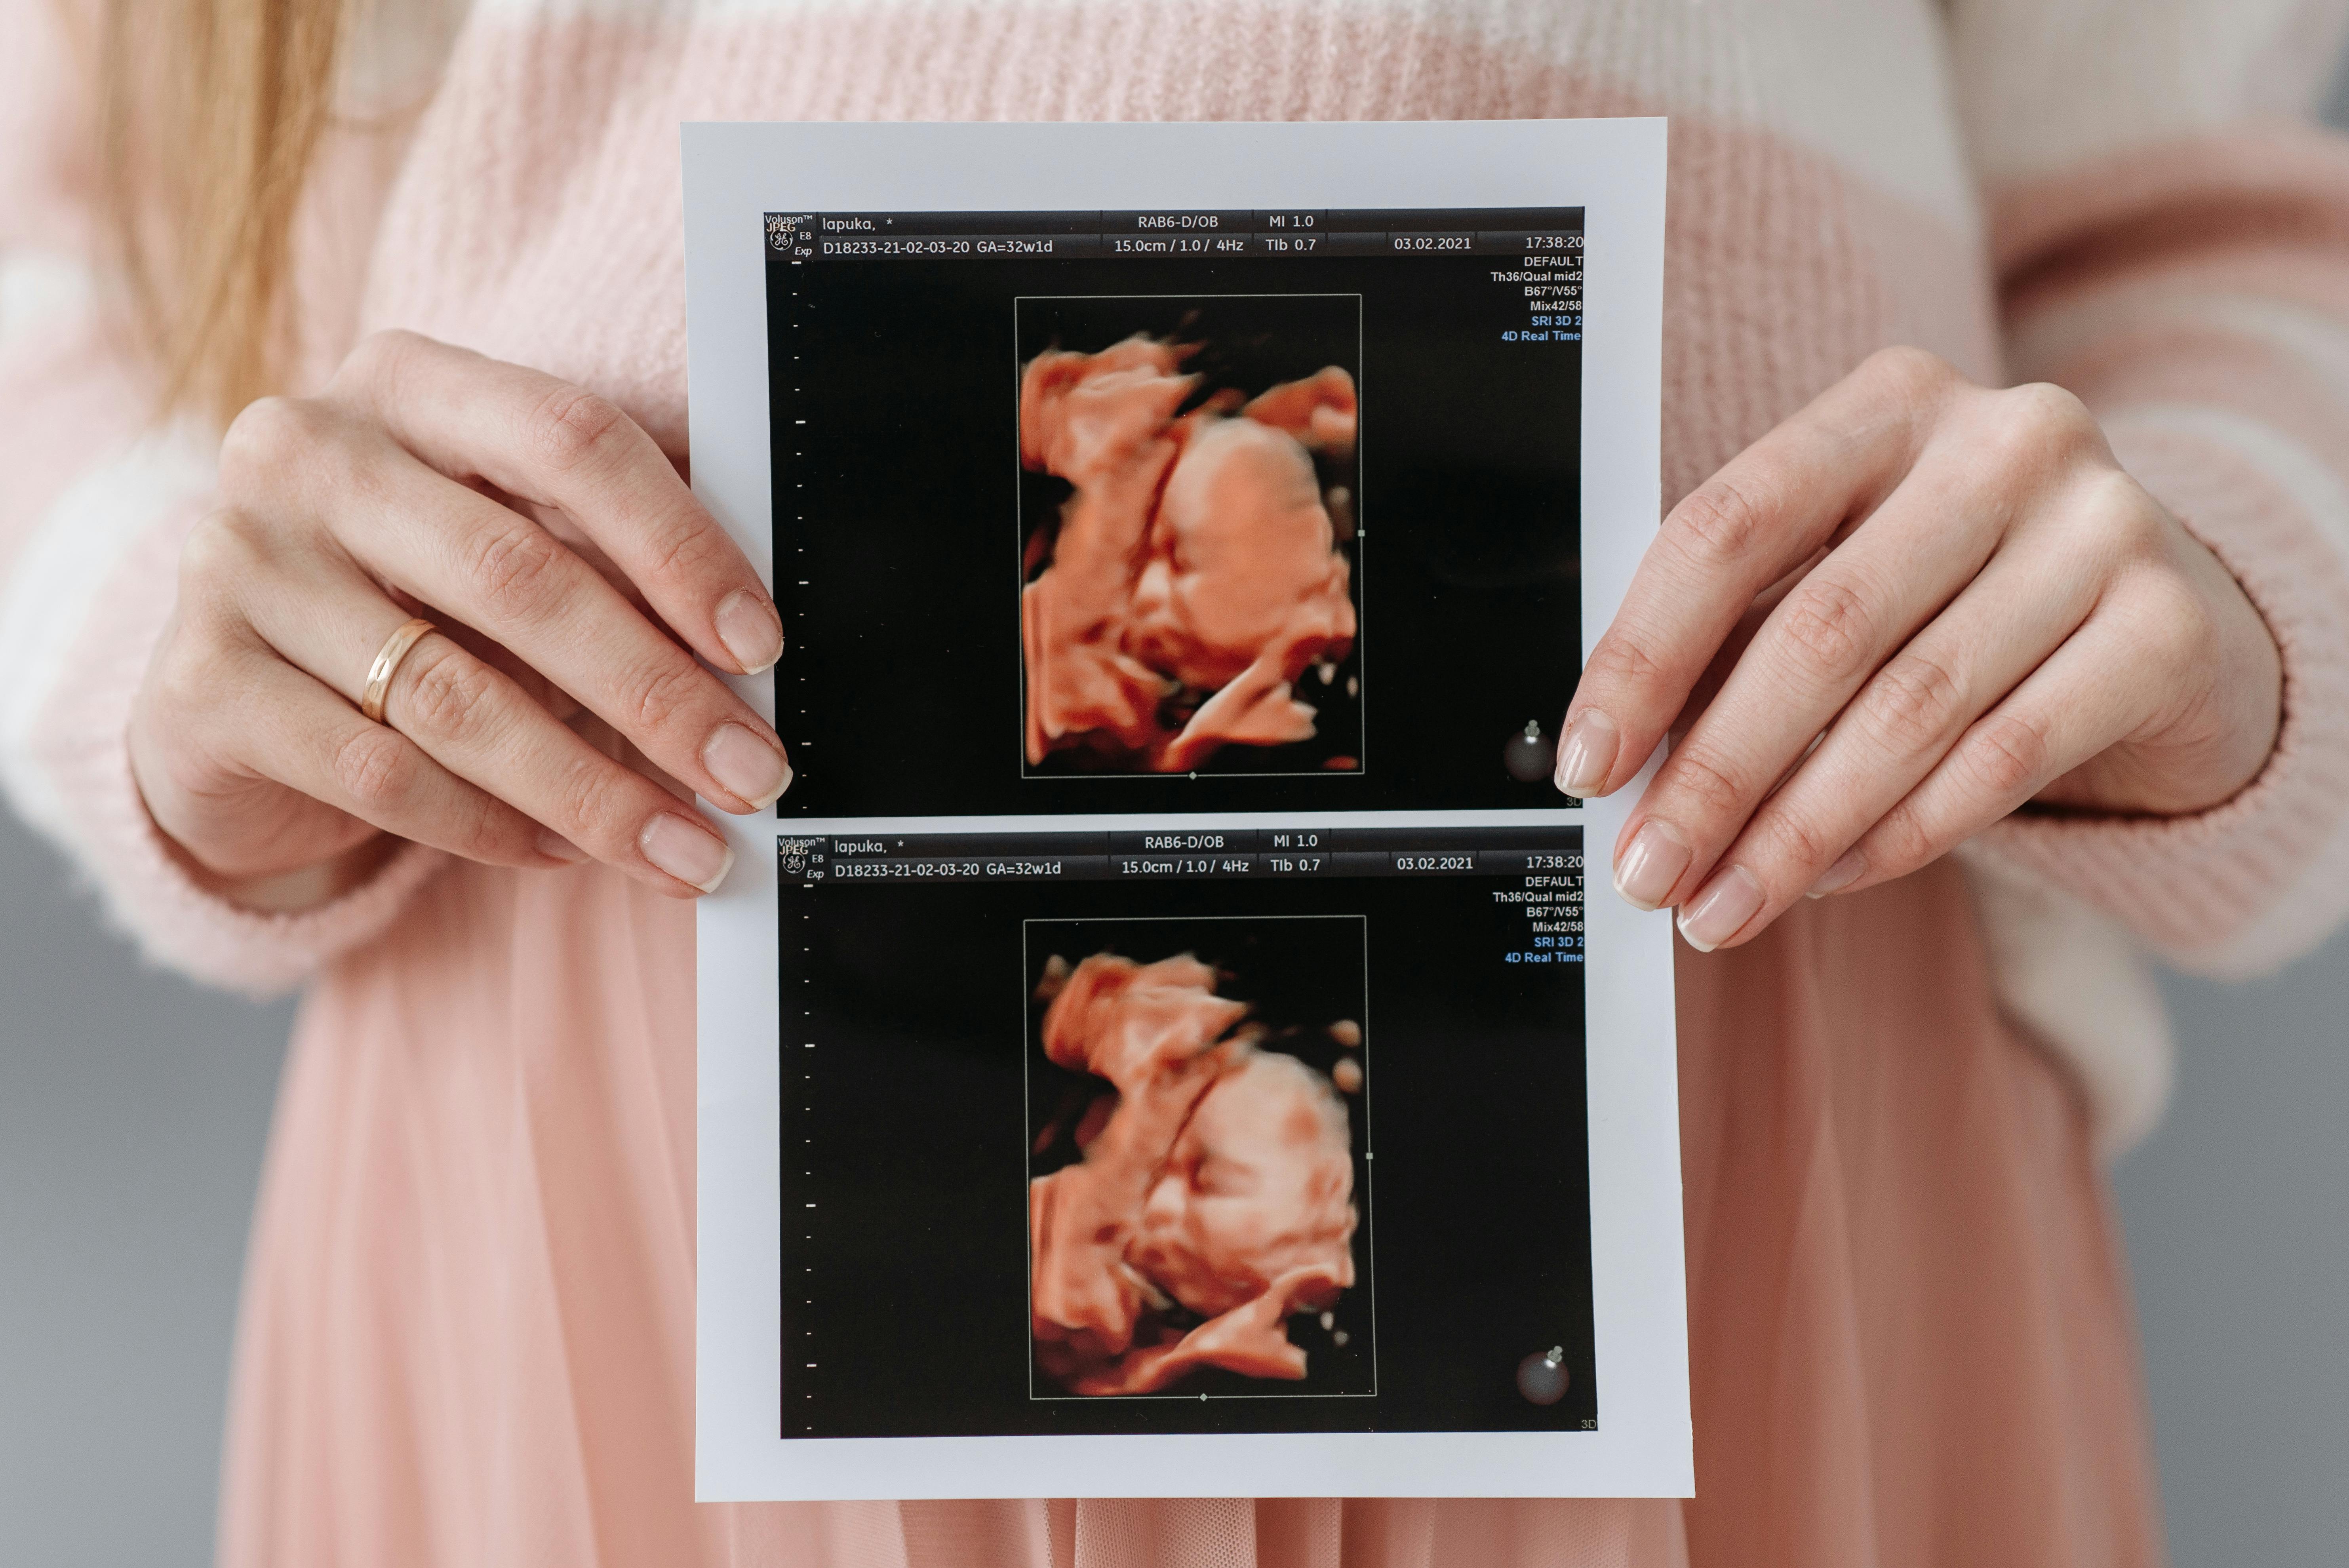

4. 시험관아기: 난자와 정자의 체외 수정

시험관아기 시술

의학용어로는 체외수정 및 배아 이식(IVF-ET)이라고 합니다. 인공수정으로는 임신이 어렵거나, 난관 폐쇄, 중증 남성 불임 등 인공수정으로 해결할 수 없는 문제에 직면한 부부들에게 적용되는 보조 생식술의 한 방법입니다. 여성의 몸 밖에서 난자와 정자를 수정시켜 배아를 만든 후, 이 배아를 다시 여성의 자궁 내로 이식하는 복잡한 과정입니다.

배아 배양 :

수정된 난자는 배아가 되고, 이 배아는 2~5일 동안 배양기에서 성장합니다. 배아의 질과 발달 상태를 매일 확인하며, 이식하기에 가장 좋은 상태의 배아를 선택합니다. 배아는 세포 분열을 거쳐 2~8세포기 배아, 상실배, 그리고 착상에 가장 적합한 상태인 배반포기 배아로 성장하게 됩니다.